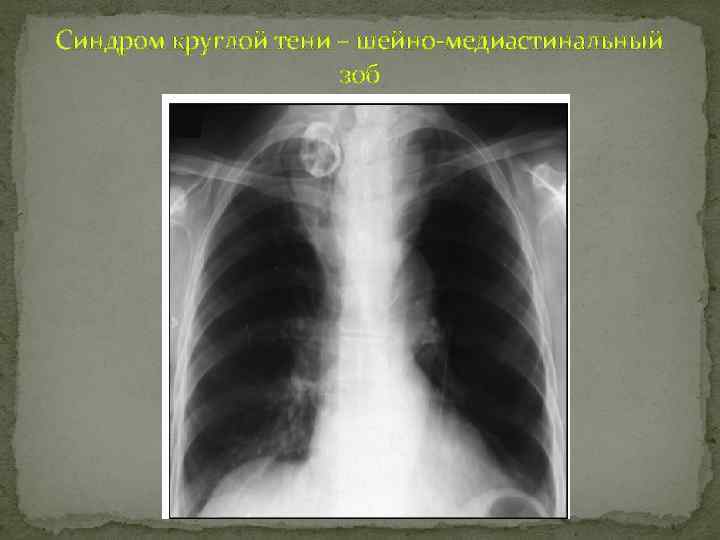

Синдром круглой тени – шейно-медиастинальный зоб